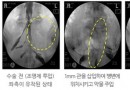

신경 성형술

국소마취하에 꼬리뼈나 목 뒤쪽의 신경공을 통하여 경막외강으로 특수바늘(카테터)을 삽입 원하는 부위에 도달하면 약물을 주입해 통증을 일으키는 염증을 가라앉히고 유착된 부위를 박리할 수 있는 치료법입니다. 일반적으로 목과 허리의 추간판 탈출증(디스크) 환자와 척추관 협착…